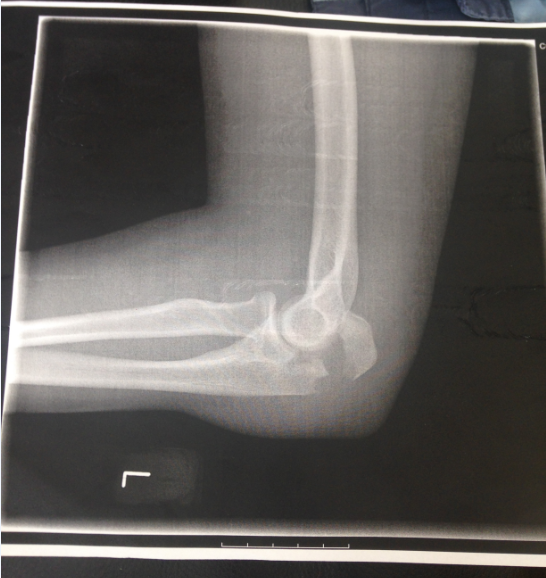

Røntgenbilleder

Før operation

- Røntgenbilledet ovenfor viser et forskudt brud på olecranon (den øverste del af albueknoglen) før operation. Forskudt vil sige, at knoglestykkerne har forskudt sig med stor afstand i forhold til den normale stilling.

- Et sådan brud behandler man med en operation, hvor knoglestykkerne sættes på plads med ståltråd, metalpinde, skruer og/eller plade.

- Ved et simpelt brud sidder knoglestykkerne stadig fint på plads, her kan man nøjes med at lægge armen i gips.